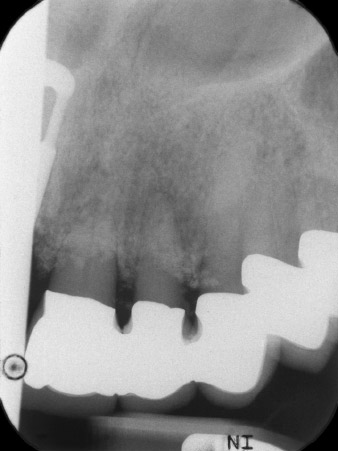

Bei der Erstvorstellung sind die Zähne 21, 22 und 23 mit 19 Jahre alten verblockten Kronen versorgt. Sie sind über ein Geschiebe mit Implantaten an den Positionen 12/11 verbunden (vgl. Abb. 2). Das Röntgenbild zeigt einen horizontalen Knochenverlust um die Zähne 21 und 22 (Abb. 1).